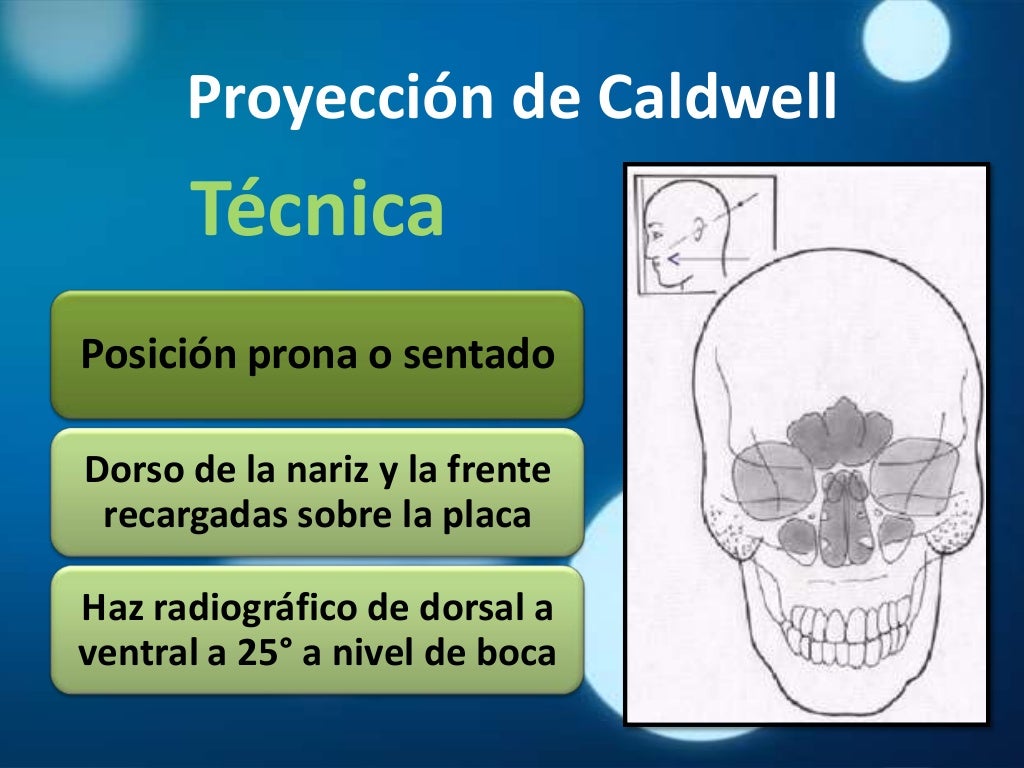

Download scientific diagram | Proyección de Waters: aumento de densidad de partes blandas de los senos maxilares (estrella) y presencia de masa en la faringe (flecha). from publication: Pólipo.. Citation, DOI, disclosures and article data. The Caldwell view is a caudally angled radiograph, with its posteroanterior projection allowing for minimal radiation to the orbits. This view may be used in imaging of the skull or facial bones depending on the clinical indications.

Proyección de Caldwell Wikiwand

Descarga RX – Posiciones Radiológicas: https://play.google.com/store/apps/details?id=com.Tarter.RXPosicionesRadiolgicas&pcampaignid=web_sharehttps://apps.app.. Study with Quizlet and memorize flashcards containing terms like Proyección de Caldwell también llamada., Proyección de Waters también llamada., ¿Qué estructuras se aprecian mejor con la proyección de Caldwell? and more.